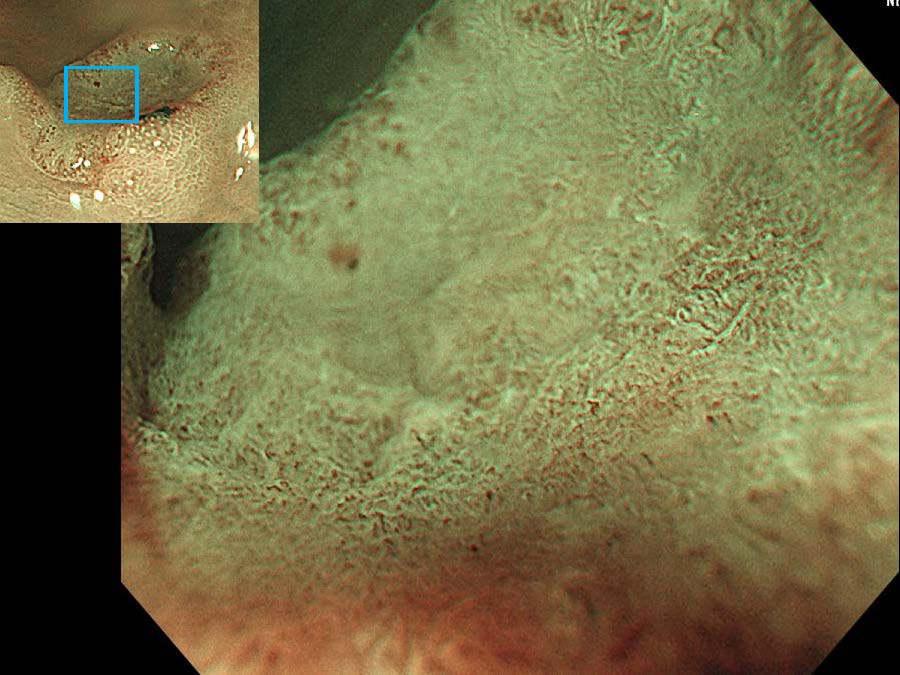

消化管Mapping~大腸~ 2021.10.27

消化管Mapping~大腸~

内視鏡検査・治療

消化管Mapping